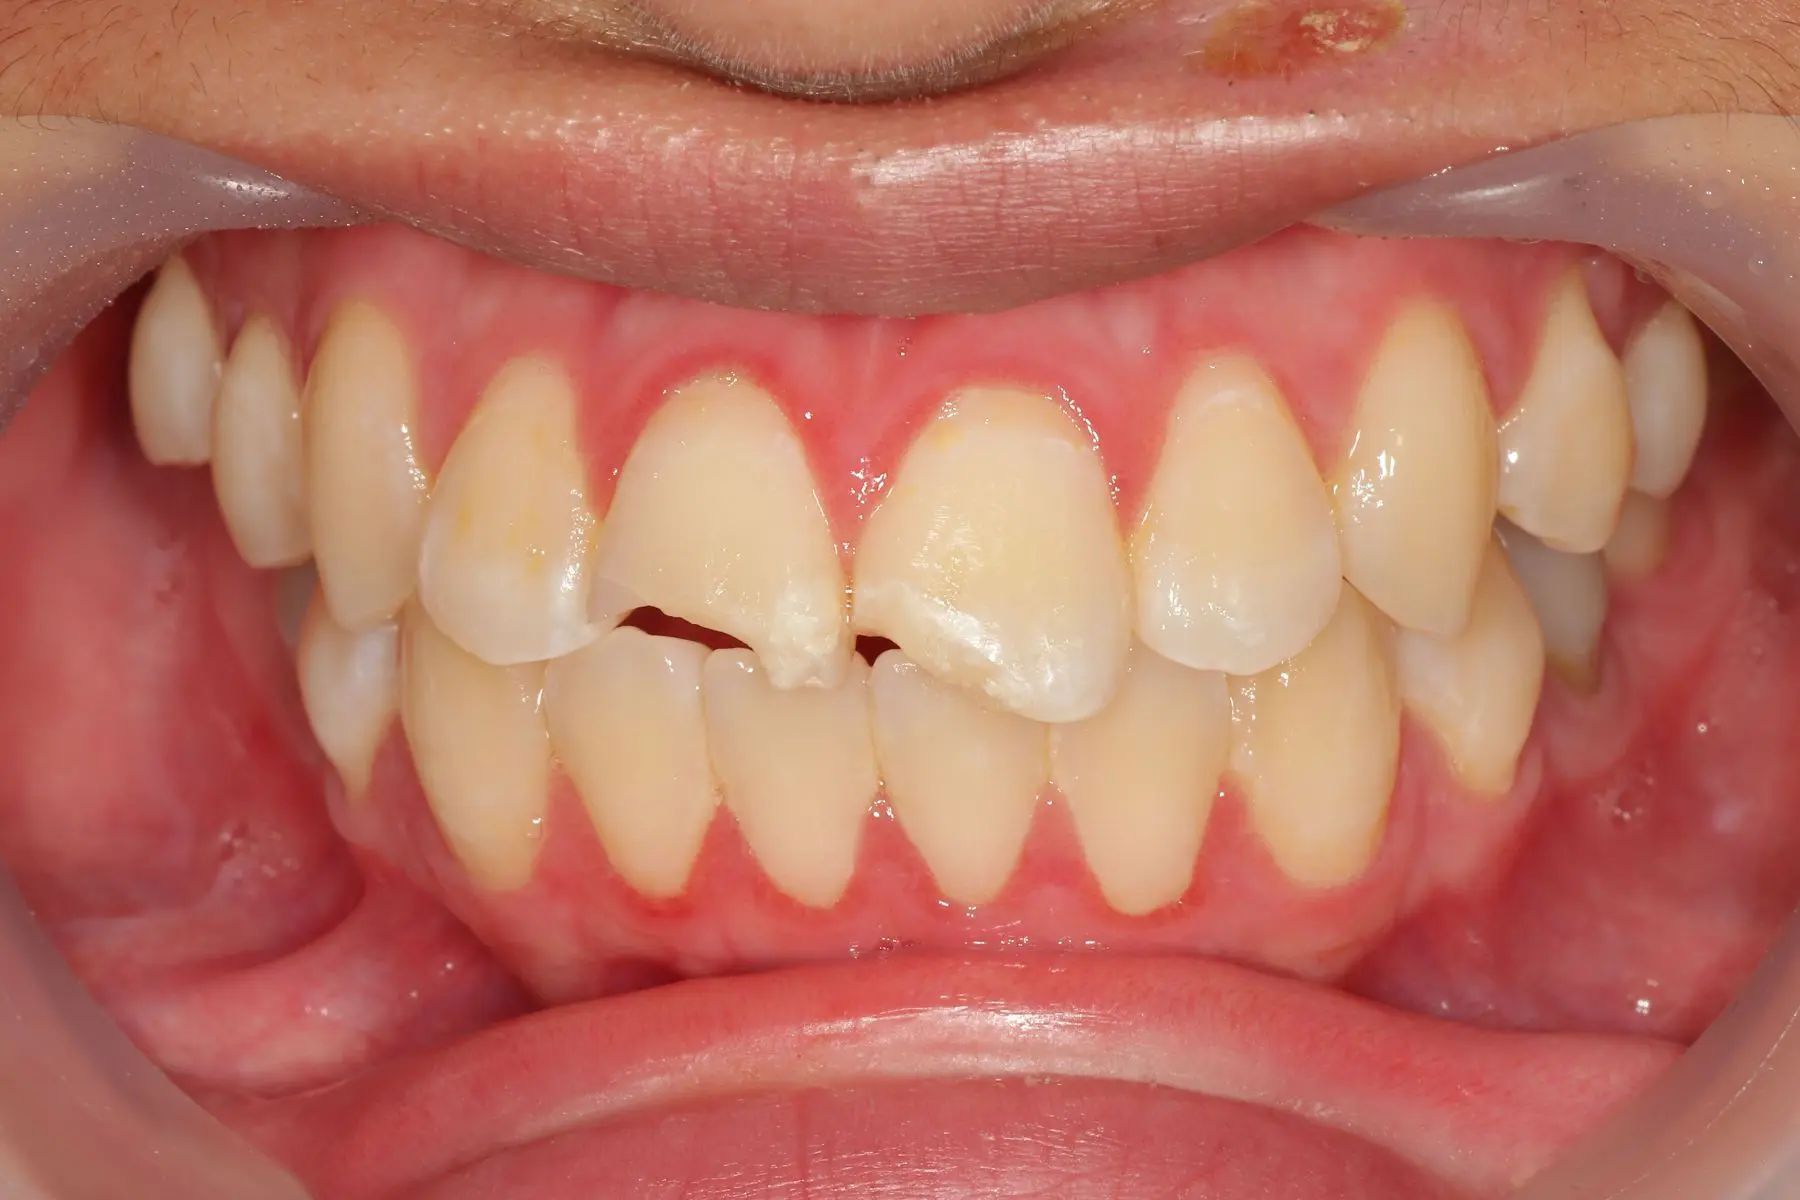

• 術前 44

術後 42

仿生美學樹脂

主治醫師

• 陳暐文

治療時間

單次療程

主訴

門牙有縫、牙齒形狀偏方,笑起來不夠自然